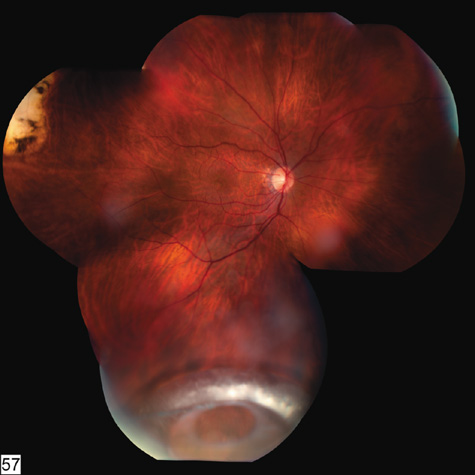

RETINAL DETACHMENT

Because men and boys are most likely to be engaged in fighting or contact sports, it is not surprising that at least three-fourths of the patients with traumatic retinal detachment are men or boys,84 and that blunt trauma is the leading cause of retinal detachment in children and adolescents.85 Because the affected patients have a formed vitreous, traumatic retinal detachments typically progress slowly unless a giant tear is present. In some patients, the trauma occurs months or years before the detachment is diagnosed. Demarcation lines, atrophy of the underlying pigment epithelium, subretinal precipitates, retinal macrocysts, and extensive vitreous “tobacco dust” are all commonly seen (Fig. 18). Proliferative vitreoretinopathy is uncommon, so the prognosis for reattachment is excellent, provided, of course, that all breaks are found. In 87% of traumatic retinal detachments, the causative tear is found at the vitreous base. Superonasal breaks at the anterior vitreous base are commonly overlooked. Because many traumatic retinal breaks cause subsequent retinal detachment, they should all be treated with laser or cryotherapy.

Fig. 18. A typical traumatic retinal detachment. There is an inferotemporal retinal dialysis, a demarcation line, and no signs of proliferative vitreoretinopathy.